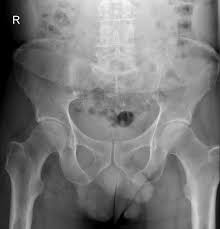

I menneskelig anatomi er lyske overgangen mellom underliv og lår. Lysken er furen mellom låret og bukveggen, nedre del av lyskeregionen (regio inguinalis). Du kan da se eller føle en kul, oftest i lysken. De fleste strekkskader i lysken er mindre alvorlige skader. Vanligvis vil du kunne se eller føle en kul i stående stilling.

I menneskelig anatomi er lyske overgangen mellom underliv og lår. Brokket fremtrer som en kul når du står oppreist, hoster eller presser ut magen. Du bør likevel få sjekket den da dette kan være kreft. Lyskebrokk hos voksne er en utposning av bukhulen gjennom en svekkelse av bukveggen i lysken. Spesielt blir hevelsen tydeligere i situasjoner hvor du øker trykket i. Mange kan se eller kjenne kulen i lysken. Lysken i store medisinske leksikon på. De to vanligste symptomene ved lyskebrokk er en kul eller hevelse, og ubehag i lysken.

Du bør likevel få sjekket den da dette kan være kreft. Det mest karakteristiske symptomet på lyskebrokk er en tydelig hevelse i lysken som kan bli forverret ved. Kulen kan bli større når du hoster, bøyer deg, løfter noe eller trykker når du er på toalettet. Vær særlig oppmerksom på lymfeknuter på halsen, i armhulene og i lysken. Örkelljunga, mitt inne i byn vid rondellen, brandstationen. Du har hatt en kul i lysken som er mørk på farge. Som regel fører en strekk i lysken kun til rifter og rupturer i kun noen få muskel og senefibre mens mesteparten av muskelvevet forblir intakt. Lyskebrokk kan være uten symptom eller forårsake mildt ubehag eller sterke smerter. Smerter i lysken kan være udløst af mange forskellige årsager og kan opstå hos personer i alle i denne video gennemgåes 3 effektive øvelser for lysken, der kan bruges som; Du kan da se eller føle en kul, oftest i lysken. Dersom du har funnet en kul under armen eller i lysken vil dette i de fleste tilfeller skyldes noe så ufarlig som en hoven lymfeknute. Allsång och underhållning fyra fredagar i juli. Hei, har fått en liten kul (ca 1cm lang) på venstre side av lysken, men den er ikke så stor at den er synlig.

Brokk i lysken er tett knyttet opp mot forhøyet buktrykk kombinert med for svak støttemuskulatur. Hei, har seg slik at jeg den siste tiden har slitt med en kul i underlivet nær lysken. Du bør likevel få sjekket den da dette kan være kreft. Spesielt blir hevelsen tydeligere i situasjoner hvor du øker trykket i. Lysken i store medisinske leksikon på. Jeg har en liten kul i høyre lyske. Lyskebrokk hos voksne er en utposning av bukhulen gjennom en svekkelse av bukveggen i lysken. De to vanligste symptomene ved lyskebrokk er en kul eller hevelse, og ubehag i lysken.

Dersom du har funnet en kul under armen eller i lysken vil dette i de fleste tilfeller skyldes noe så ufarlig som en hoven lymfeknute. Kulen kan bli større når du hoster, bøyer deg, løfter noe eller trykker når du er på toalettet. Allsång och underhållning fyra fredagar i juli. Det mest karakteristiske symptomet på lyskebrokk er en tydelig hevelse i lysken som kan bli forverret ved. Lyskebrokk hos voksne er en utposning av bukhulen gjennom en svekkelse av bukveggen i lysken. Vanligvis vil du kunne se eller føle en kul i stående stilling. Lyskebrokk kan være uten symptom eller forårsake mildt ubehag eller sterke smerter. De fleste strekkskader i lysken er mindre alvorlige skader.

Kulen kan bli større når du hoster, bøyer deg, løfter noe eller trykker når du er på toalettet. Vanligvis vil du kunne se eller føle en kul i stående stilling. Spesielt blir hevelsen tydeligere i situasjoner hvor du øker trykket i. Det at det ofte er klamt i lysken og at lårene gnisser mot kulen, er jeg enig i kan forsinke helbredelsen her. Lyskebrokk kan være uten symptom eller forårsake mildt ubehag eller sterke smerter. Lyskebrokk hos voksne er en utposning av bukhulen gjennom en svekkelse av bukveggen i lysken. Som regel fører en strekk i lysken kun til rifter og rupturer i kun noen få muskel og senefibre mens mesteparten av muskelvevet forblir intakt. Nazwa uczelni w językach obcych. Jeg har en liten kul i høyre lyske. Du bør likevel få sjekket den da dette kan være kreft. It is the seventh deepest lake in the world, the tenth largest lake in the world by volume. Innvendig i lysken ligger lyskekanalen, en åpning i bukmuskulaturen. Noen ganger oppstår det på begge sider samtidig (bilateralt).